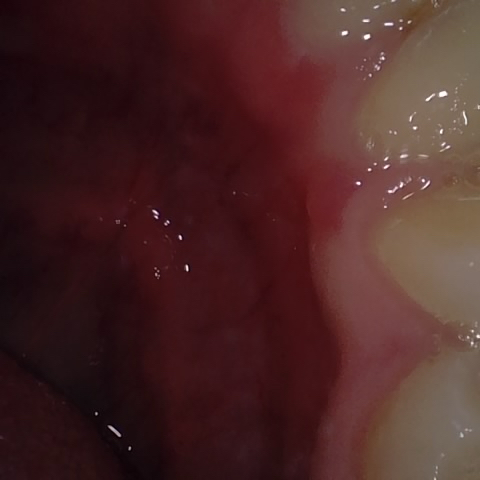

Annotated as "Bad"